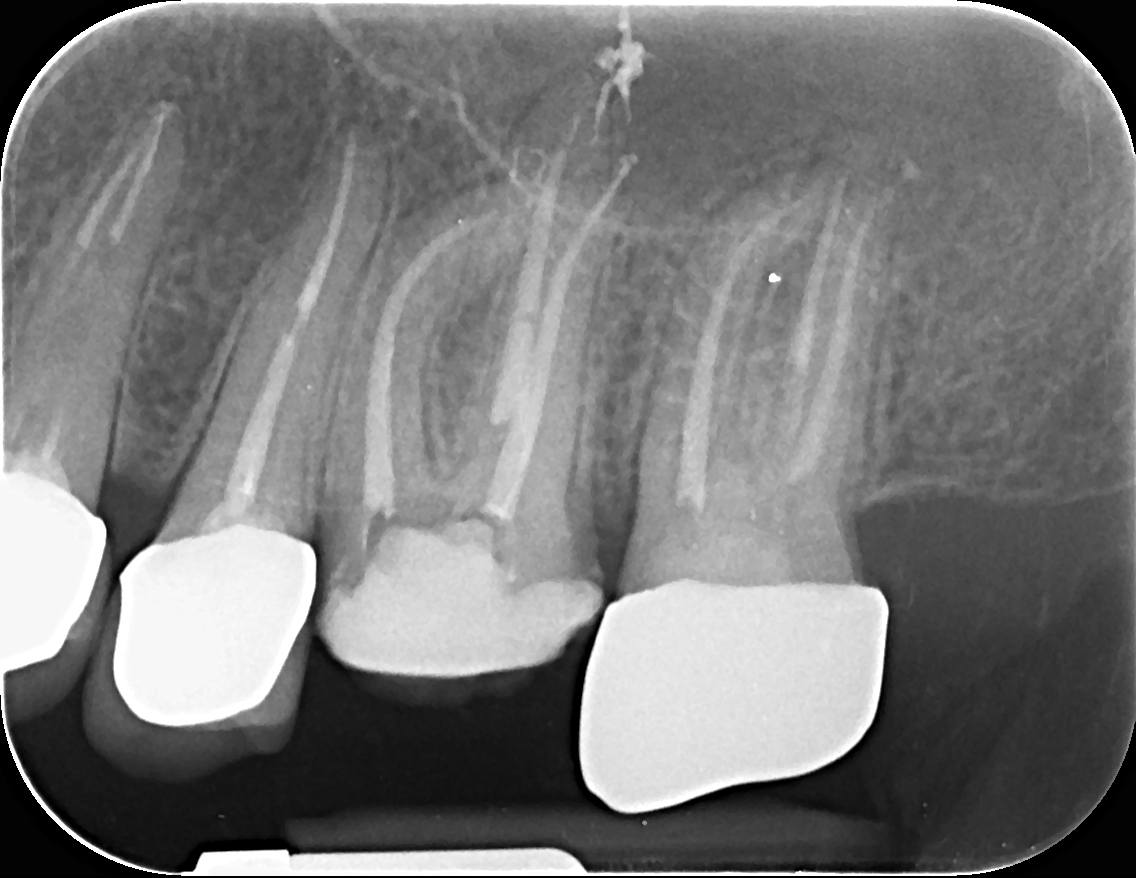

Pacienții necesită un tratament endodontic atunci când la nivelul camerei pulpare sau a canalului radicular există inflamație sau infecție, din cauza unei carii profunde, a unei fisuri sau provocată de un traumatism accidental. Poate fi realizat într-o singură ședință sau în mai multe, în funcție de complexitatea cazului.

În timpul tratamentului, medicul endodont curăță, dezinfectează, prepară canalele radiculare și obturează etanș spațiul creat. Dinții cu destrucții coronare masive necesită ranforsare cu pivoți de fibră de sticlă, iar ulterior vor fi șlefuiți și acoperiți cu lucrări protetice ce redau rezistența structurii dentare restante.